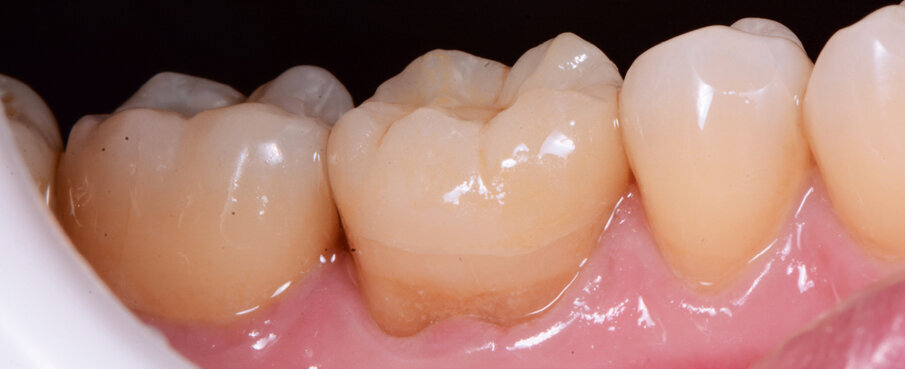

Figs. 12a & b: Lateral and occlusal views of the completed restoration.

A 45-year-old male patient presented to the practice with a restoration on tooth #46. The tooth had been endodontically treated and temporised with a filling (Fig. 1). The temporary was removed, the tooth built up with Tetric N-Ceram Bulk Fill (Ivoclar Vivadent) and then prepared for the crown restoration (Fig. 2). An impression was taken with a one- step, two-phase impression technique using a putty and light-body silicone. After scanning the model, the crown was designed in the software suite (inLab, Dentsply Sirona) and milled from an IPS e.max CAD lithium disilicate block (Ivoclar Vivadent; Figs.3a & b). After the crystallisation fir- ing, the crown was stained and glazed (Fig. 4). The next step was to etch and silanate the ceramic crown with the new glass-ceramic primer Monobond Etch & Prime (Ivoclar Vivadent). This primer combines a ceramic etching and silanating component in a single material and therefore eliminates the need for the ceramic to undergo hydrofluoric acid etching (Fig. 5). After the etching and silanating step, the crown was rinsed with water and dried. The isolated enamel was then etched (Fig. 6). The adhesive (Tetric N-Bond Universal) was applied and dispersed with a strong stream of air. The dual-curing version of the Variolink Esthetic luting composite was used for seating owing to the thickness of the crown and the low translucency of the ceramic material (Fig. 7). The luting composite was applied into the crown. The restoration was then seated (Fig. 8) and light-cured from each side for two seconds. Excess composite was easy to remove owing to the Ivocerin photoinitiator (Ivoclar Vivadent), which provides a fast and thorough cure with a minimum amount of energy (Fig. 9). For final polymerisation, the restoration was light-cured from each quarter for 20 seconds (Fig. 10). Figures 11 and 12a & b show the oral situation after placement of the crown. Although the cement line was located above the gingival margin, it was not visible owing to the favourable tone and opacity of the luting composite. Figures 13a & b show radiographic control images of the restoration: the radiopaque build-up material and cement can easily be distinguished from the tooth structure. This aspect is particularly important in situations where excess cement cannot be seen with the naked eye.